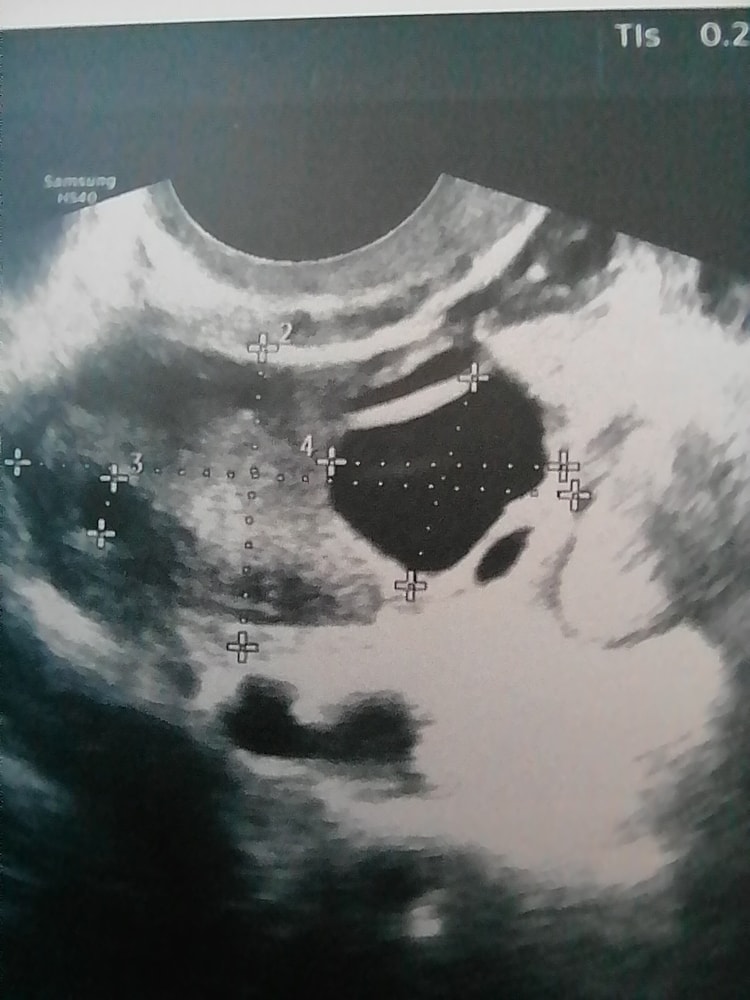

Изображение

Укол ХГЧ Фолликулометрия на полный мочевой